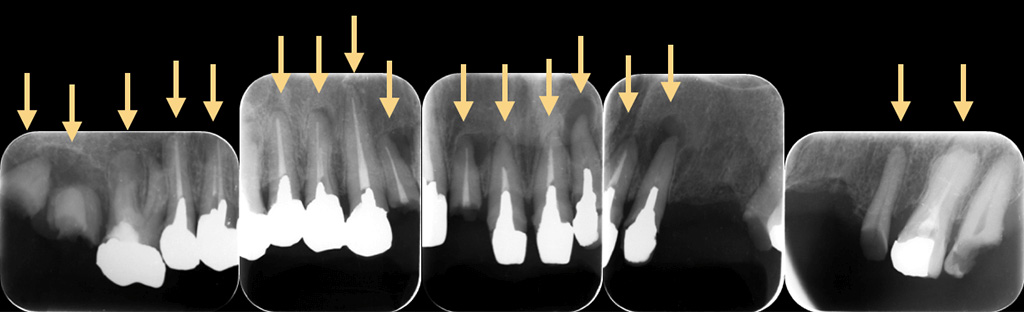

盲点であるのは、過去にむし歯治療をした歯です。一見キレイに銀歯が入っているように見えます。しかも銀歯で全周覆われているので、むし歯菌が歯に侵入しないように思えますが、実際はどうでしょうか?

金属のかぶせを外すとこのようにむし歯でボロボロになってしまっているのがわかります。なぜこのようになってしまったかというと、歯と金属のかぶせ物の間に隙間があったからです。むし歯菌は目に見えないほど小さく、むし歯菌の侵入を防ぐには、精度の高いかぶせ物を作る必要があります。